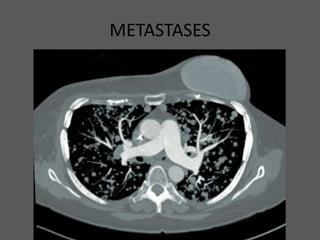

METASTASES